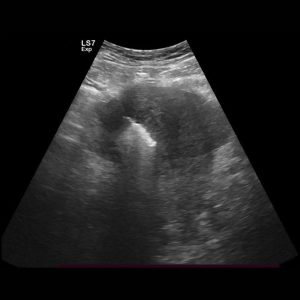

Our Solution: Using ultrasound guidance, a thin probe is placed into the fibroid or adenomyotic tissue. Radiofrequency or Microwave energy safely heats and destroys the targeted tissue.

1. Uterine Fibroid & Adenomyosis Ablation (RFA/MWA)

The Problem: Fibroids and adenomyosis can cause heavy, painful periods, pelvic pressure, and can impact fertility.